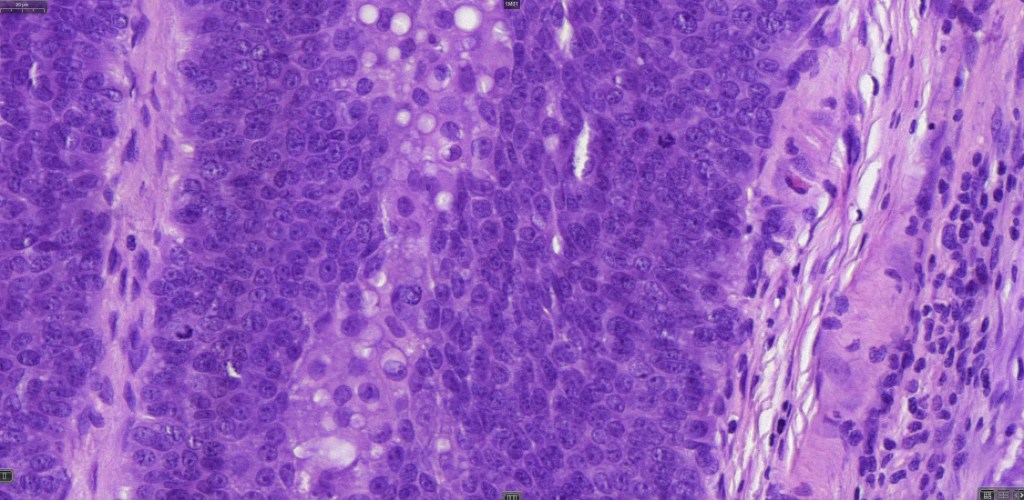

•Well differentiated examples can be deceptive unless one looks carefully for pleomorphism, necrosis, excessive mitotic activity and abnormal mitoses. Be careful diagnosing sebaceous adenoma, particularly large examples arising in the elderly

•Tumors are composed of an admixture of darkly staining basaloid cells with hyperchromatic or vesicular nuclei and more obvious sebaceous cells with eosinophilic, bubbly, multivacuolated cytoplasm frequently indenting the nucleus (scalloped)

•Often mitoses are numerous and abnormal forms evident

•Variable Lymphovascular invasion & perineural infiltration

Sebaceous carcinoma from a patient with Muir-Torre syndrome kindly shared by Dr. Antonina Kalmykova.